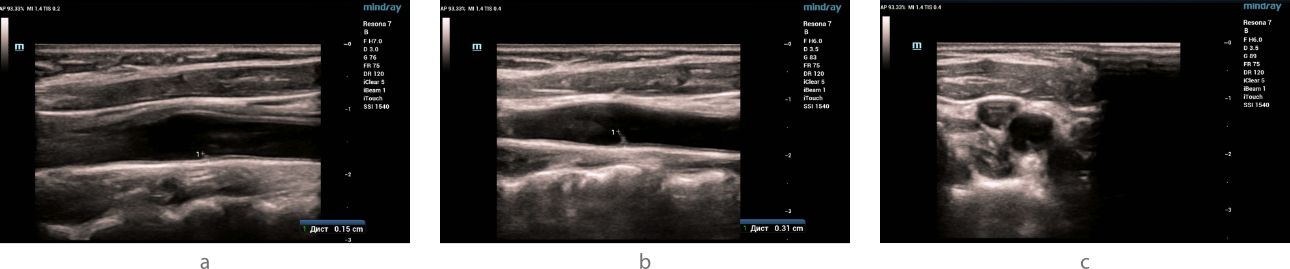

Ultrasound examination - B- mode

Ultrasound examination (ultrasound) of the carotid and vertebral arteries was performed on the Resona 7 ultrasound machine (Mindray, China) using the L9-3U linear probe. When examined in B-mode in the area of bifurcation of the common carotid artery, a hyperechoic linear structure (slightly expanding at the base) with clear even contours, without signs of flotation, having a slope towards the internal carotid artery and protruding into the lumen of the vessel was visualized on both sides along the posterior wall: on the right by 1.5 mm, on the left by 3.1 mm (fig. 1). No structural changes were detected in other carotid and vertebral arteries.

In the bifurcation of the common carotid artery, markers indicate a linear hyperechoic signal with dimensions on the right (a) and left (b) in the longitudinal scanning plane. The type of hyperechoic signal (indicated by the arrow) in the left common carotid artery in the transverse scanning plane (c).